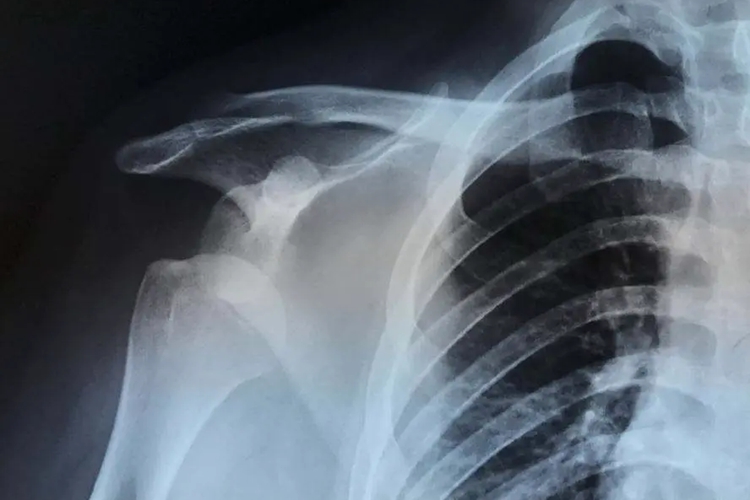

肩关节半脱位,早期患者可无任何不适感,部分患者当患侧上肢在体侧垂放时间较长时,可出现牵拉不适感或疼痛,当上肢被支撑或抬起时,上述症状可减轻或消失。随着时间的延长可出现明显肩痛及肩关节活动受限,肩峰与肱骨头之间可触及明显凹陷。X检查时可见肩峰及肱骨头间隙增大。